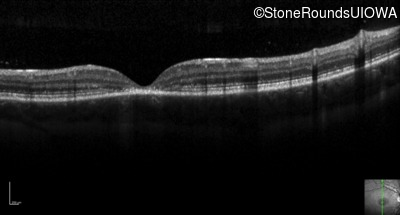

Optical Coherence Tomography - Left - 20/80 -2 sc

Exemplar / OCT Stack